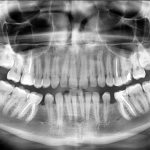

X-ray

X-ray examination is used in dentistry to study the structure and condition of the bone tissue of the jaw and teeth. It allows you to build a competent treatment plan and predict its results.

For radiological diagnosis of dentofacial anomalies, the following radiological methods :

• Orthopantomography . Allows you to obtain a panoramic image of the problem jaw with a detailed image of each element.